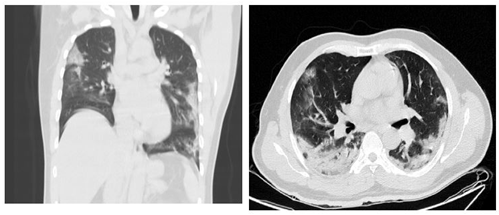

Por deterioro en los índices de oxigenación y del estado clínico general fue traslado a la unidad de cuidados intensivos para manejo ventilatorio invasivo. Se realizó tomografía de tórax de alta resolución, encontrando infiltrado en vidrio esmerilado subpleural periférico y patrón “Crazy paving” (o empedrado) comprometiendo los cuatro cuadrantes del parénquima pulmonar (figuras 1A y 1B). Estos hallazgos son altamente sugestivos de infección por COVID-19, por lo que se continuó manejo médico de soporte y protocolo para síndrome de dificultad respiratoria aguda bajo sospecha de infección por SARS-CoV-2.

Figura 1A y 1B. Imágenes del TACAR con Infiltrados subpleurales bilaterales en bases y lóbulos medio, con patrón “Crazy Paving” de cuatro cuadrantes del parénquima pulmonar. Hallazgos sugestivos de infección por COVID-19.